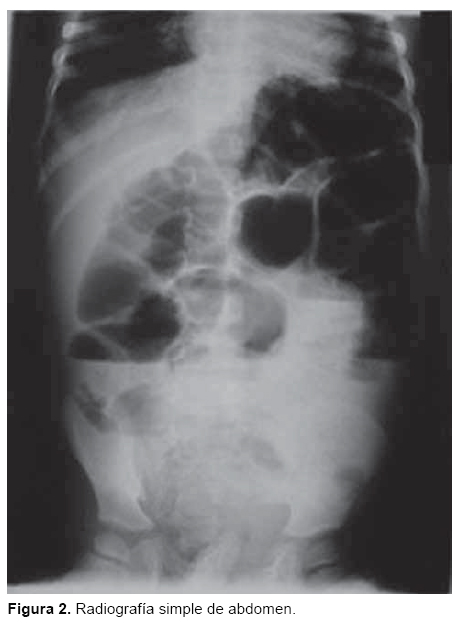

Se trató de paciente masculino de 6 años de edad, originario de Pichucalco, Chiapas, que presentó un cuadro de 24 horas de evolución, caracterizado por dolor abdominal, fiebre, vómitos y ausencia de evacuaciones. A la exploración física, se apreciaba delgado, con facies de dolor. Cardiopulmonar sin compromiso. Abdomen con datos de abdomen agudo, caracterizado por presencia de dolor abdominal difuso, rebote positivo e irritación abdominal, signos de Me Burney, Rovsing y Blumberg positivos, distensión abdominal leve y ausencia de peristaltismo. Presentó edema leve y eritema de hemiescroto derecho (Figura 1). La biometría hemática reportó anemia leve, Hb 9.5, leucocitosis 15,000, segmentados 80%, con 5% de bandas, eosinofilos 5%. Se realizó una radiografía simple de abdomen, de pie, donde se apreció mala distribución de aire, niveles hidroaereos, ausencia de aire en hueco pélvico y opacidad difusa central. No se observaron calcificaciones, ni columna antiálgica, ni fecalitos (Figura 2). Con los datos anteriores y ante el cuadro de abdomen agudo, se decidió realizar laparotomía exploradora, con diagnóstico preoperatorio de probable apendicitis complicada vs abdomen agudo secundario a hernia incarcerada. Por esta razón se realizó una incisión transversa infraumbilical derecha tipo Rocky-Davis. Se encontró apéndice "normal" con hiperemia; posteriormente se revisó el ileón terminal y se localizó divertículo de Meckel a 75 cm de la válvula. Se encontró perforado en su punta (Figura 3) con peritonitis leve, por lo que se realizó resección y enteroanastomosis íleo-ileal. Al realizar el lavado exhaustivo de la cavidad abdominal con solución fisiológica se encontraron, sorpresivamente, dos Ascaris lumbricoides de 25 cm, libres entre las asas intestinales. Por esta razón, se decidió realizar "taxis" del contenido intestinal yeyuno ileal (madeja de Ascaris) que hasta el momento había pasado inadvertido hacia el colon. Se realizó la limpieza de la cavidad con lavado (profuso) con 2 litros de solución fisiológica, y antes de cerrar pared abdominal por planos, se tocó y exploró el hemiescroto derecho. Se palpó tumefacto y crepitante, por lo que se decidió realizar la exploración del canal inguinal derecho. Se encontró un Ascaris lumbricoides hembra, adulta, de 25 cm, enroscada en la túnica vaginalis del testículo derecho (Figura 4). Se extrajo y se realizó la plastia inguinal, lavándose en forma exhaustiva. Se indicaron antibióticos intravenosos y ayuno por 7 días. Se inició la vía oral al séptimo día. Se observó una evolución satisfactoria y se dio de alta sin presentar complicaciones. con controles periódicos a 2 años de la cirugía.

Por las características de este paciente, el cuadro clínico de abdomen agudo sugiere, en primer lugar, apendicitis aguda complicada, por ser la causa más frecuente de urgencia abdominal en niños.8 Sin embargo, el cuadro clínico del paciente sugiere varios diagnósticos diferenciales con otras patologías, como perforación intestinal por Salmonella, hernia inguinal derecha estrangulada, vólvulos o probable obstrucción por divertículo de Meckel, entre otros.3 En el preoperatorio, no se sospechó de complicaciones quirúrgicas por ascaridiasis, ya que no se contaba con antecedentes de expulsión de Ascaris por tubo digestivo y la radiografía no demostraba el clásico "migajón de pan" de la ascaridiasis.5,6